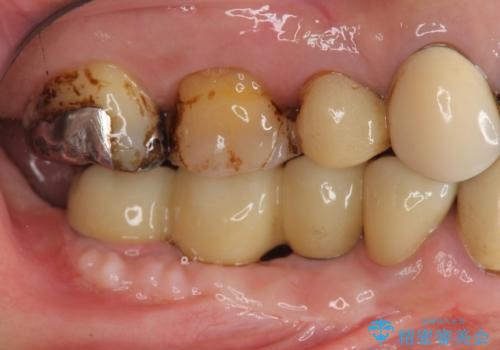

- インプラント治療を希望し数軒の医院で治療の相談をするも、骨の量が足りず治療が難しいと断られたのち当院にも相談にみえました。

長年の義歯の使用により骨の幅は非常に薄くインプラントを埋入するには大規模な骨の造成が必要な状態です。